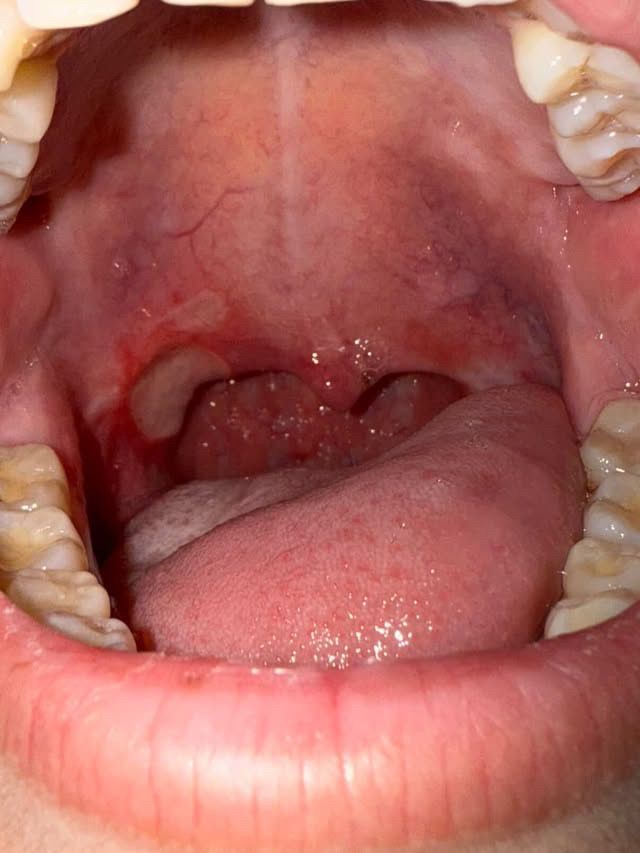

편고수술후 편도부위에 구내염같은게 생겼어요 재수술해야하나요?

3달전에 편도수술을 하고 잘지내고있었는데 갑자기 목쪽에 구내염같은게 생겨서 병원에 가보니 염즘이라고 약만 먹었는데 일주일이 지나도 났질않고 점점커지며 피까지 납니다 재수술을 해야할까요

• 2번 째 사진